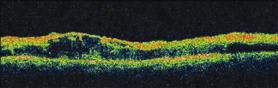

Visual acuity was 20/160 in the right eye and 20/250 in the left eye. She had the relative afferent papillary defect in the left eye. Anterior-segment examination was unremarkable. Dilated fundus examination demonstrated scattered cotton wool spots and intraretinal hemorrhages in the posterior pole and midperiphery, and macular edema in both eyes (Figures 1A, 1B, 1C, 1D). Fluorescein angiography showed marked capillary nonperfusion in the macula and periphery with vascular leakage in the late frames (Figures 2A, 2B, 2C, 2D). Optical coherence tomography showed cystoid retinal thickening in both maculae (Figures 3A and 3B).

Figure 3A. OCT of the right macula shows severe cystoid thickening of the retina.

Figure 3B. OCT of the left macula shows thickening of the retina.